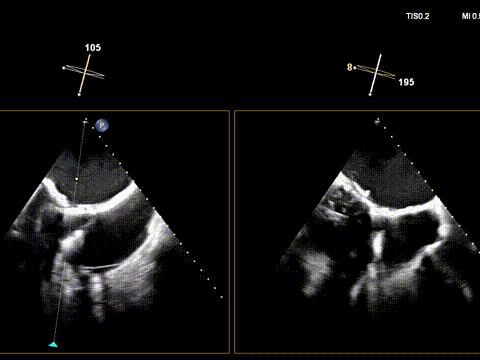

经右颈内静脉穿刺建立通路,置入18Fr鞘管,将K-Clip®输送系统送达右心房。依托三维经食管超声心动图(3D TEE)联合 DSA 双模态引导,经验精准定位瓣环,于后隔交界(P-S commissure)植入14T规格K-Clip®,前后交界(A-P commissure)植入16T规格K-Clip®,实现瓣环多点精准环缩。每枚夹子释放后,团队实时通过超声评估瓣叶对合及反流改善情况,严格遵循 “精准定位 - 锚定验证 - 安全解离” 的规范化操作流程,确认无瓣叶损伤、瓣口狭窄及心包并发症后,完成器械解离与撤出。

5. 第二枚夹子同样操作,三维下夹子形态稳定

1. 瓣环面积由18.7降至11.9,瓣环面积减少36%。

2. 术前反流4+降至1+。